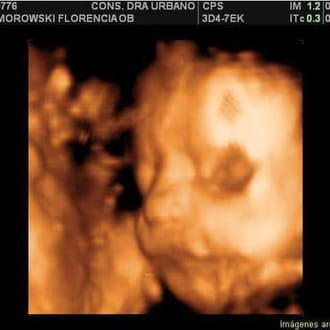

Hola, Chivas tengo una gran duda hoy el ginecologo me dijo que no ve al feto y que hay dos opciones una de que el feto es de 2 a 3 semanas y aun no lo...